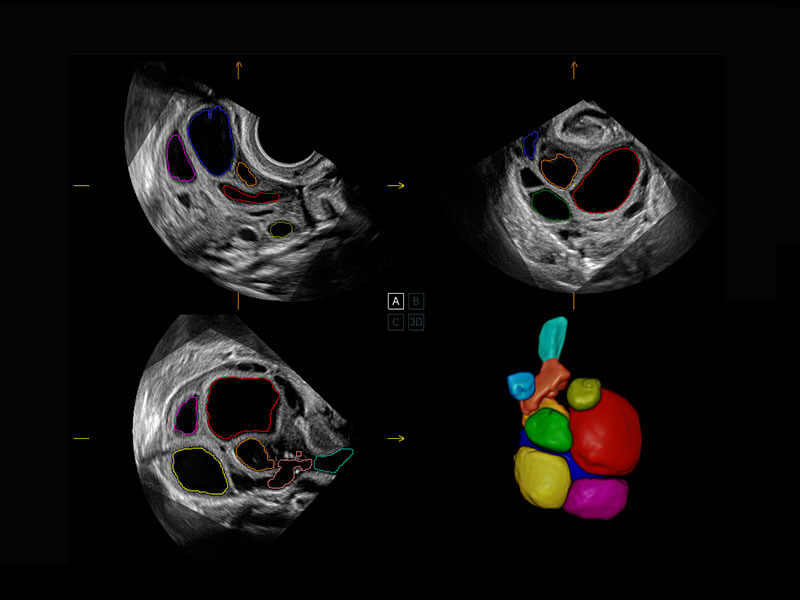

中晚孕筛查

P60提供简单易学易用的高端诊断工具,为您中晚孕筛查提供快速清晰的解剖信息。

S-Fetus(acq.)

& S-Fetus(meas.)

S-Fetus

S-Fetus能够助您在实时扫查过程中自动识别标准切面、自动测量并录入报告。一个按键,即可快速、高效地获取胎儿生理指标,简化您的产科检查操作。